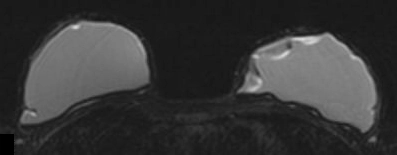

Túi ngực (breast implants)